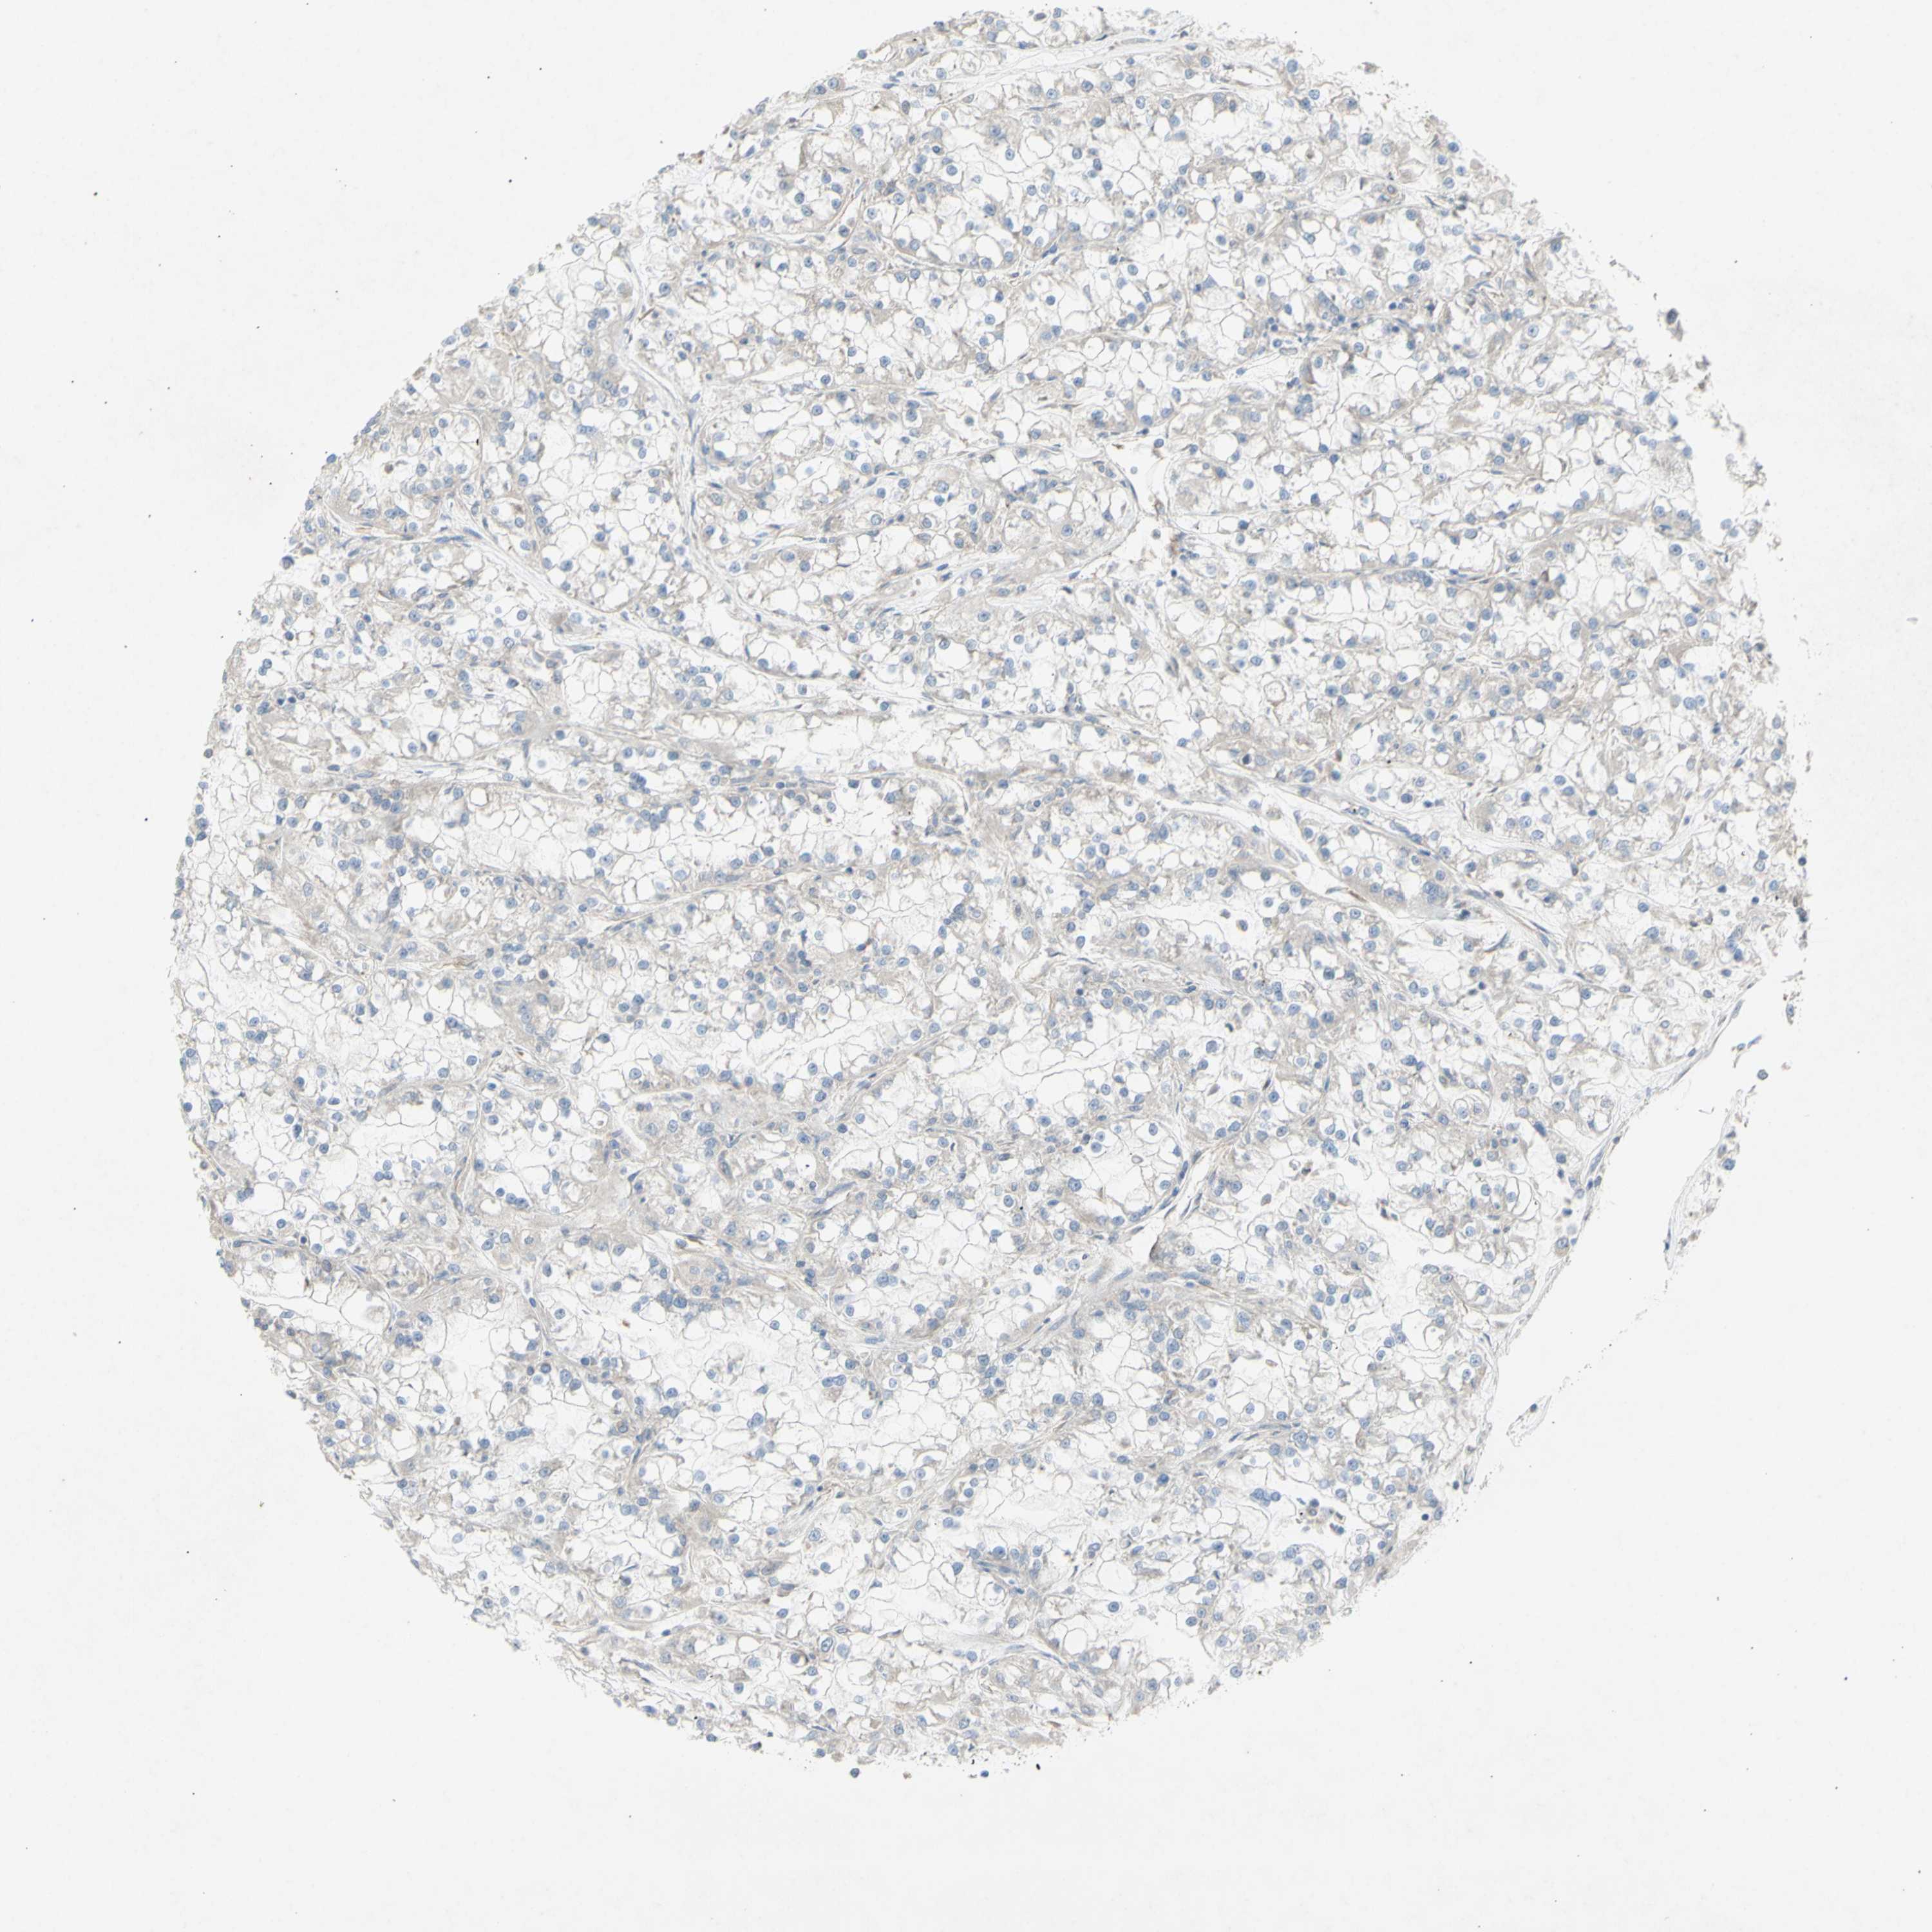

KIDNEY RENAL PAPILLARY CELL CARCINOMA (TCGA) - Interactive survival scatter ploti

The Survival Scatter plot shows the clinical status (i.e. dead or alive) for all individuals in the patient cohort, based on the same data that underlies the corresponding Kaplan-Meier plots. Patients that are alive at last time for follow-up are shown in blue and patients who have died during the study are shown in red.

The x-axis shows the expression levels (FPKM) of the investigated gene in the tumor tissue at the time of diagnosis. The y-axis shows the follow-up time after diagnosis (years). Both axes are complimented with kernel density curves demonstrating the data density over the axes. The top density plot shows the expression levels (FPKM) distribution among dead (red) and alive patients (blue). The right density plot shows the data density of the survived years of dead patients with high and low expression levels respectively, stratified using the cutoff indicated by the vertical dashed line through the Survival Scatter plot. This cutoff is automatically defined based on the FPKM cutoff that minimizes the p-score. The cutoff can be changed by dragging the vertical line or by entering a cutoff value in the square labeled "Current cut-off".

Under the Survival Scatter plot the p-score landscape (black curve; left axis) is shown together with dead median separation (red curve; right axis). Dead median separation is the difference in median mRNA expression between patients who have died with high and low expression, respectively. It is calculated as follows: median FPKM expression of dead patients with high expression - median FPKM expression of dead patients with low expression. This is intended to aid the user in visually exploring custom cutoffs and the associated p-scores and dead median separation.

Individual patient data is displayed and can be filtered by clicking on one or more of the category buttons on the top of the page. Categories describing expression level and patient information include: high, low, alive, dead, female, male and tumor stages. The scale of the x-axis can be toggled between linear and log-scale by clicking on the "x log" button. Mouse-over function shows TCGA ID, patient information and mRNA expression (FPKM) for each patient.

& Survival analysisi

Kaplan-Meier plots summarize results from analysis of correlation between mRNA expression level and patient survival. Patients were divided based on level of expression into one of the two groups "low" (under cut off) or "high" (over cut off). X-axis shows time for survival (years) and y-axis shows the probability of survival, where 1.0 corresponds to 100 percent.

KLC1 is not prognostic in Kidney Renal Papillary Cell Carcinoma (TCGA)